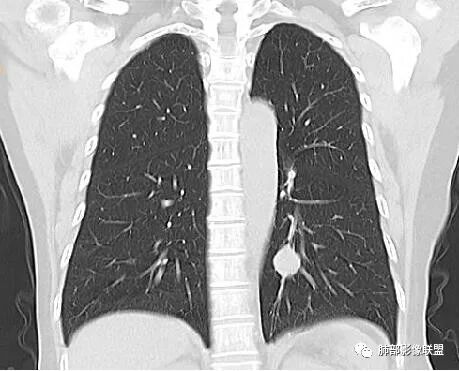

目前大家意见一致一米阳光:左肺下叶类圆形病灶,边缘清晰,密度均匀,无分叶毛刺等恶性征像,增强,病变明显强化,血管贴边支持PSP,鉴别类癌,后者弱强化,貌似有分叶南边:

崔刚:当时写报告看好像是支气管确实没堵,受压的改变。

横断位应该显示了这个支气管,当时记得特意考下来图了

M-Imaging :周围有黑边,错构呢?南边:如果明确没堵塞就好办这个最主要的就是这个支气管是否堵塞没堵塞,支持PSP杨泽锋:如果是气管腔内起源的那就要考虑类癌M-Imaging :不见明显冰山征,没有钙化南边:心里不是很踏实,就是没看到支气管全景Forever:强化如果不高 我还是考虑小细胞肺癌或者腺癌

Shelia:隆突下没看到肿大淋巴结呀南边:那就是支气管应该是堵了。图少了一点

wonderful:纵膈有吗徐超:隆突下没有肿大淋巴结。思路没问题,主要还是支气管的关系。还有CT值,有测量值最好。强化不同疾病范围不同,虽然有叠加Coke with ice:这个病灶好像有浅分叶,是否有鉴别意义呢南边:可能绕过去了。浅分叶没什么价值,深分叶有Forever:动脉期强化不太均匀 而且ct值不高我觉得有提示意义

1.图片未能提供病灶与支气管的确切关系,支气管截断有助于大细胞癌或腺癌的判断,管腔狭窄有助于小细胞癌的判断。